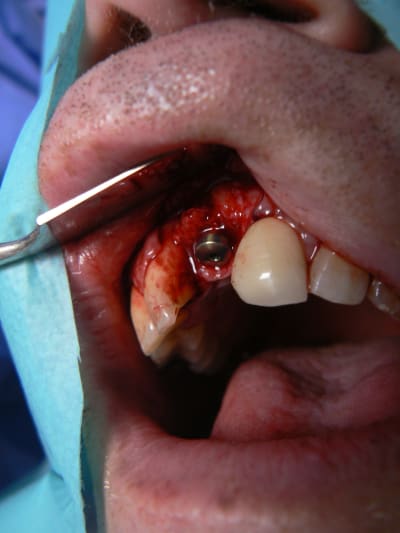

j'ai retrouvé, mais c'est le correspondant qui à posé l'implant et les photos sont pas top :(

j'essaie d'envoyer si ça marche

ceux sont les photos du correspondant .